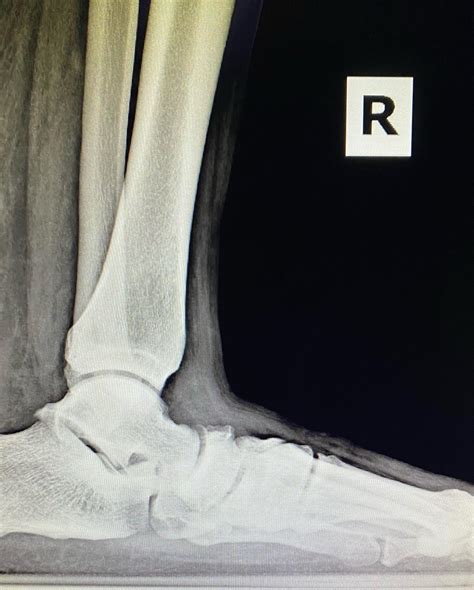

Capital Foot & Ankle Surgeons of Austin | Austin TX